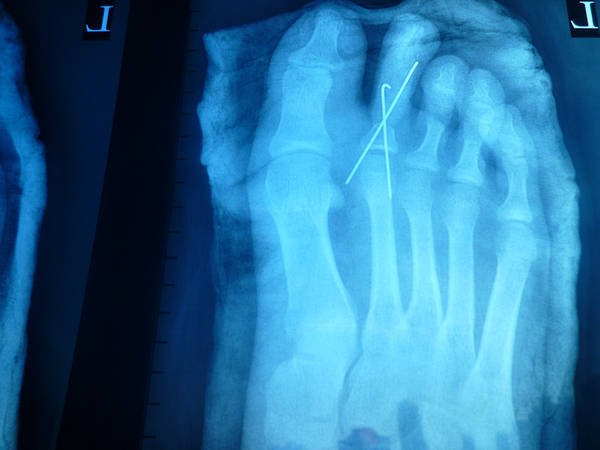

今天拍的术后情况

皮瓣还是没做好有点臃肿!下次注意